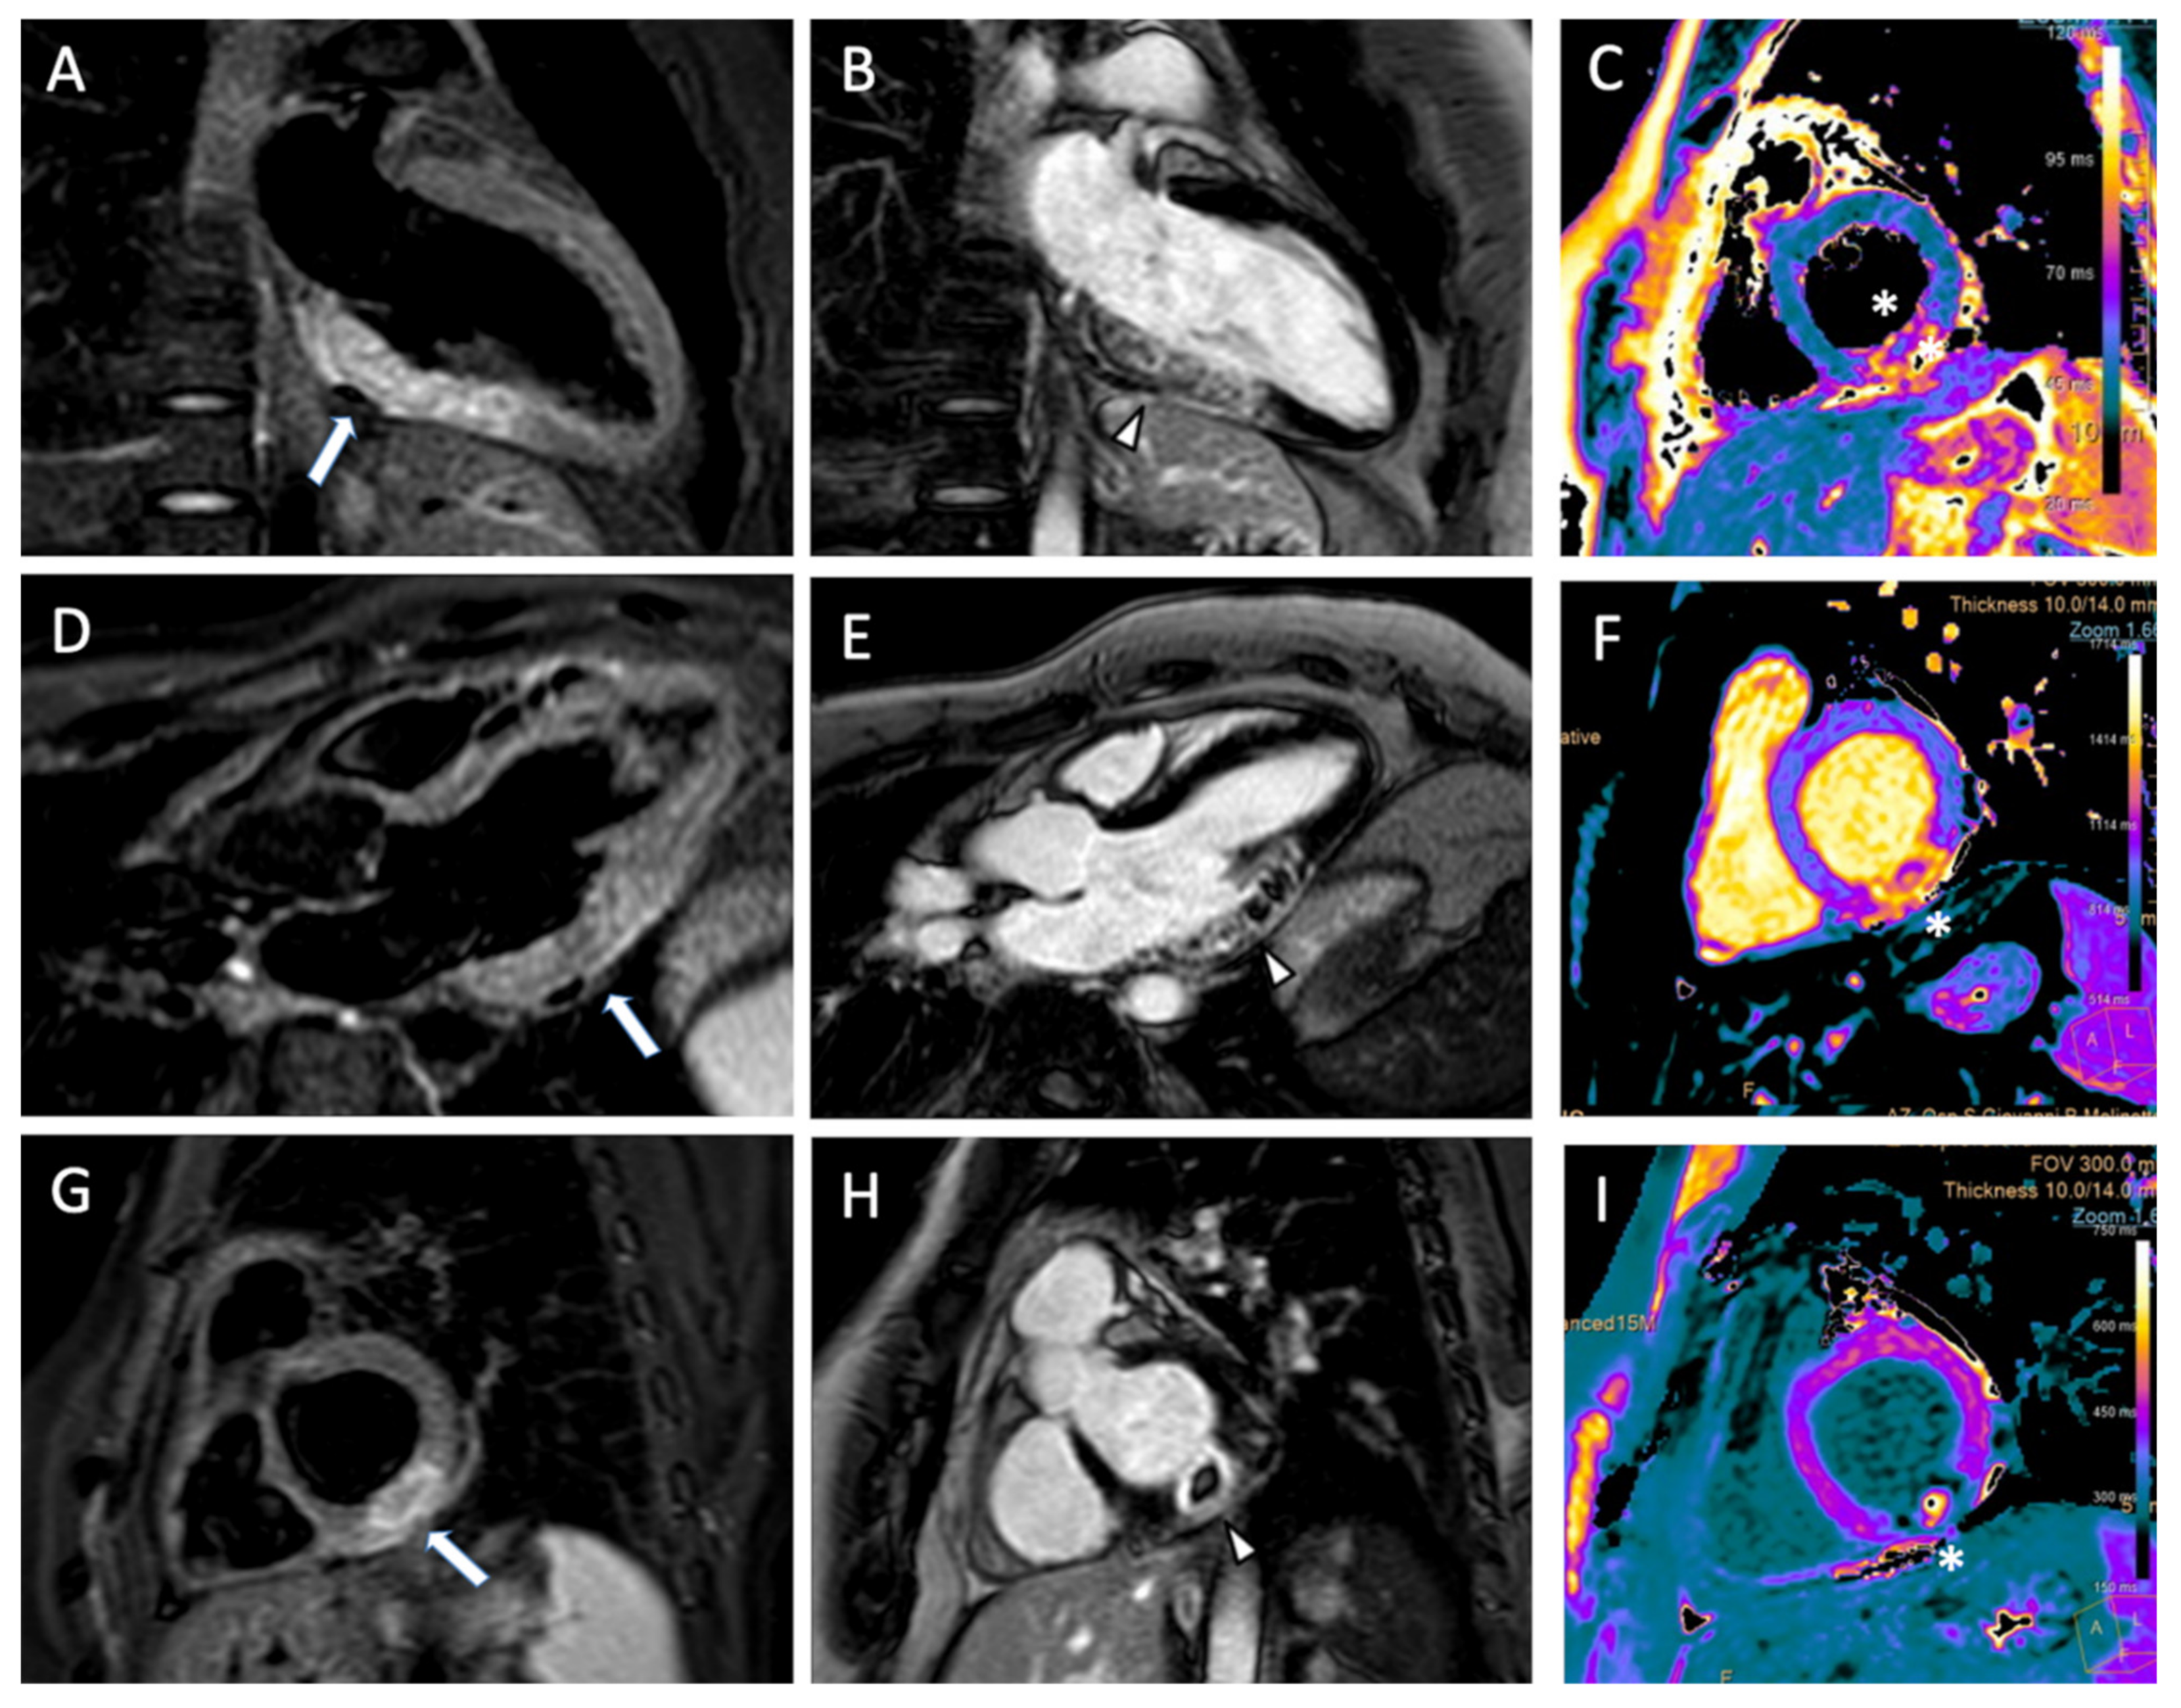

- Muscogiuri, G.; Ricci, F.; Scafuri, S.; Guglielmo, M.; Baggiano, A.; De Stasio, V.; Di Donna, C.; Spiritigliozzi, L.; Chiocchi, M.; Lee, S.J.; et al. Cardiac Magnetic Resonance Tissue Characterization in Ischemic Cardiomyopathy. J. Thorac. Imaging 2022, 37, 2–16. [Google Scholar] [CrossRef] [PubMed]

- Kim, H.W.; Van Assche, L.; Jennings, R.B.; Wince, W.B.; Jensen, C.J.; Rehwald, W.G.; Wendell, D.C.; Bhatti, L.; Spatz, D.M.; Parker, M.A.; et al. Relationship of T2-Weighted MRI Myocardial Hyperintensity and the Ischemic Area-At-Risk. Circ. Res. 2015, 117, 254–265. [Google Scholar] [CrossRef]

- Muscogiuri, G.; Suranyi, P.; Schoepf, U.J. Cardiac Magnetic Resonance T1-Mapping of the Myocardium: Technical Background and Clinical Relevance. J. Thorac. Imaging 2018, 33, 71–80. [Google Scholar] [CrossRef]

- Giri, S.; Chung, Y.-C.; Merchant, A.; Mihai, G.; Rajagopalan, S.; Raman, S.V.; Simonetti, O.P. T2 quantification for improved detection of myocardial edema. J. Cardiovasc. Magn. Reson. 2009, 11, 56. [Google Scholar] [CrossRef]

- Bulluck, H.; White, S.K.; Rosmini, S.; Bhuva, A.N.; Treibel, T.A.; Fontana, M.; Abdel-Gadir, A.; Herrey, A.S.; Manisty, C.H.; Wan, S.M.Y.; et al. T1 mapping and T2 mapping at 3T for quantifying the area-at-risk in reperfused STEMI patients. J. Cardiovasc. Magn. Reson. 2015, 17, 73. [Google Scholar] [CrossRef] [PubMed]